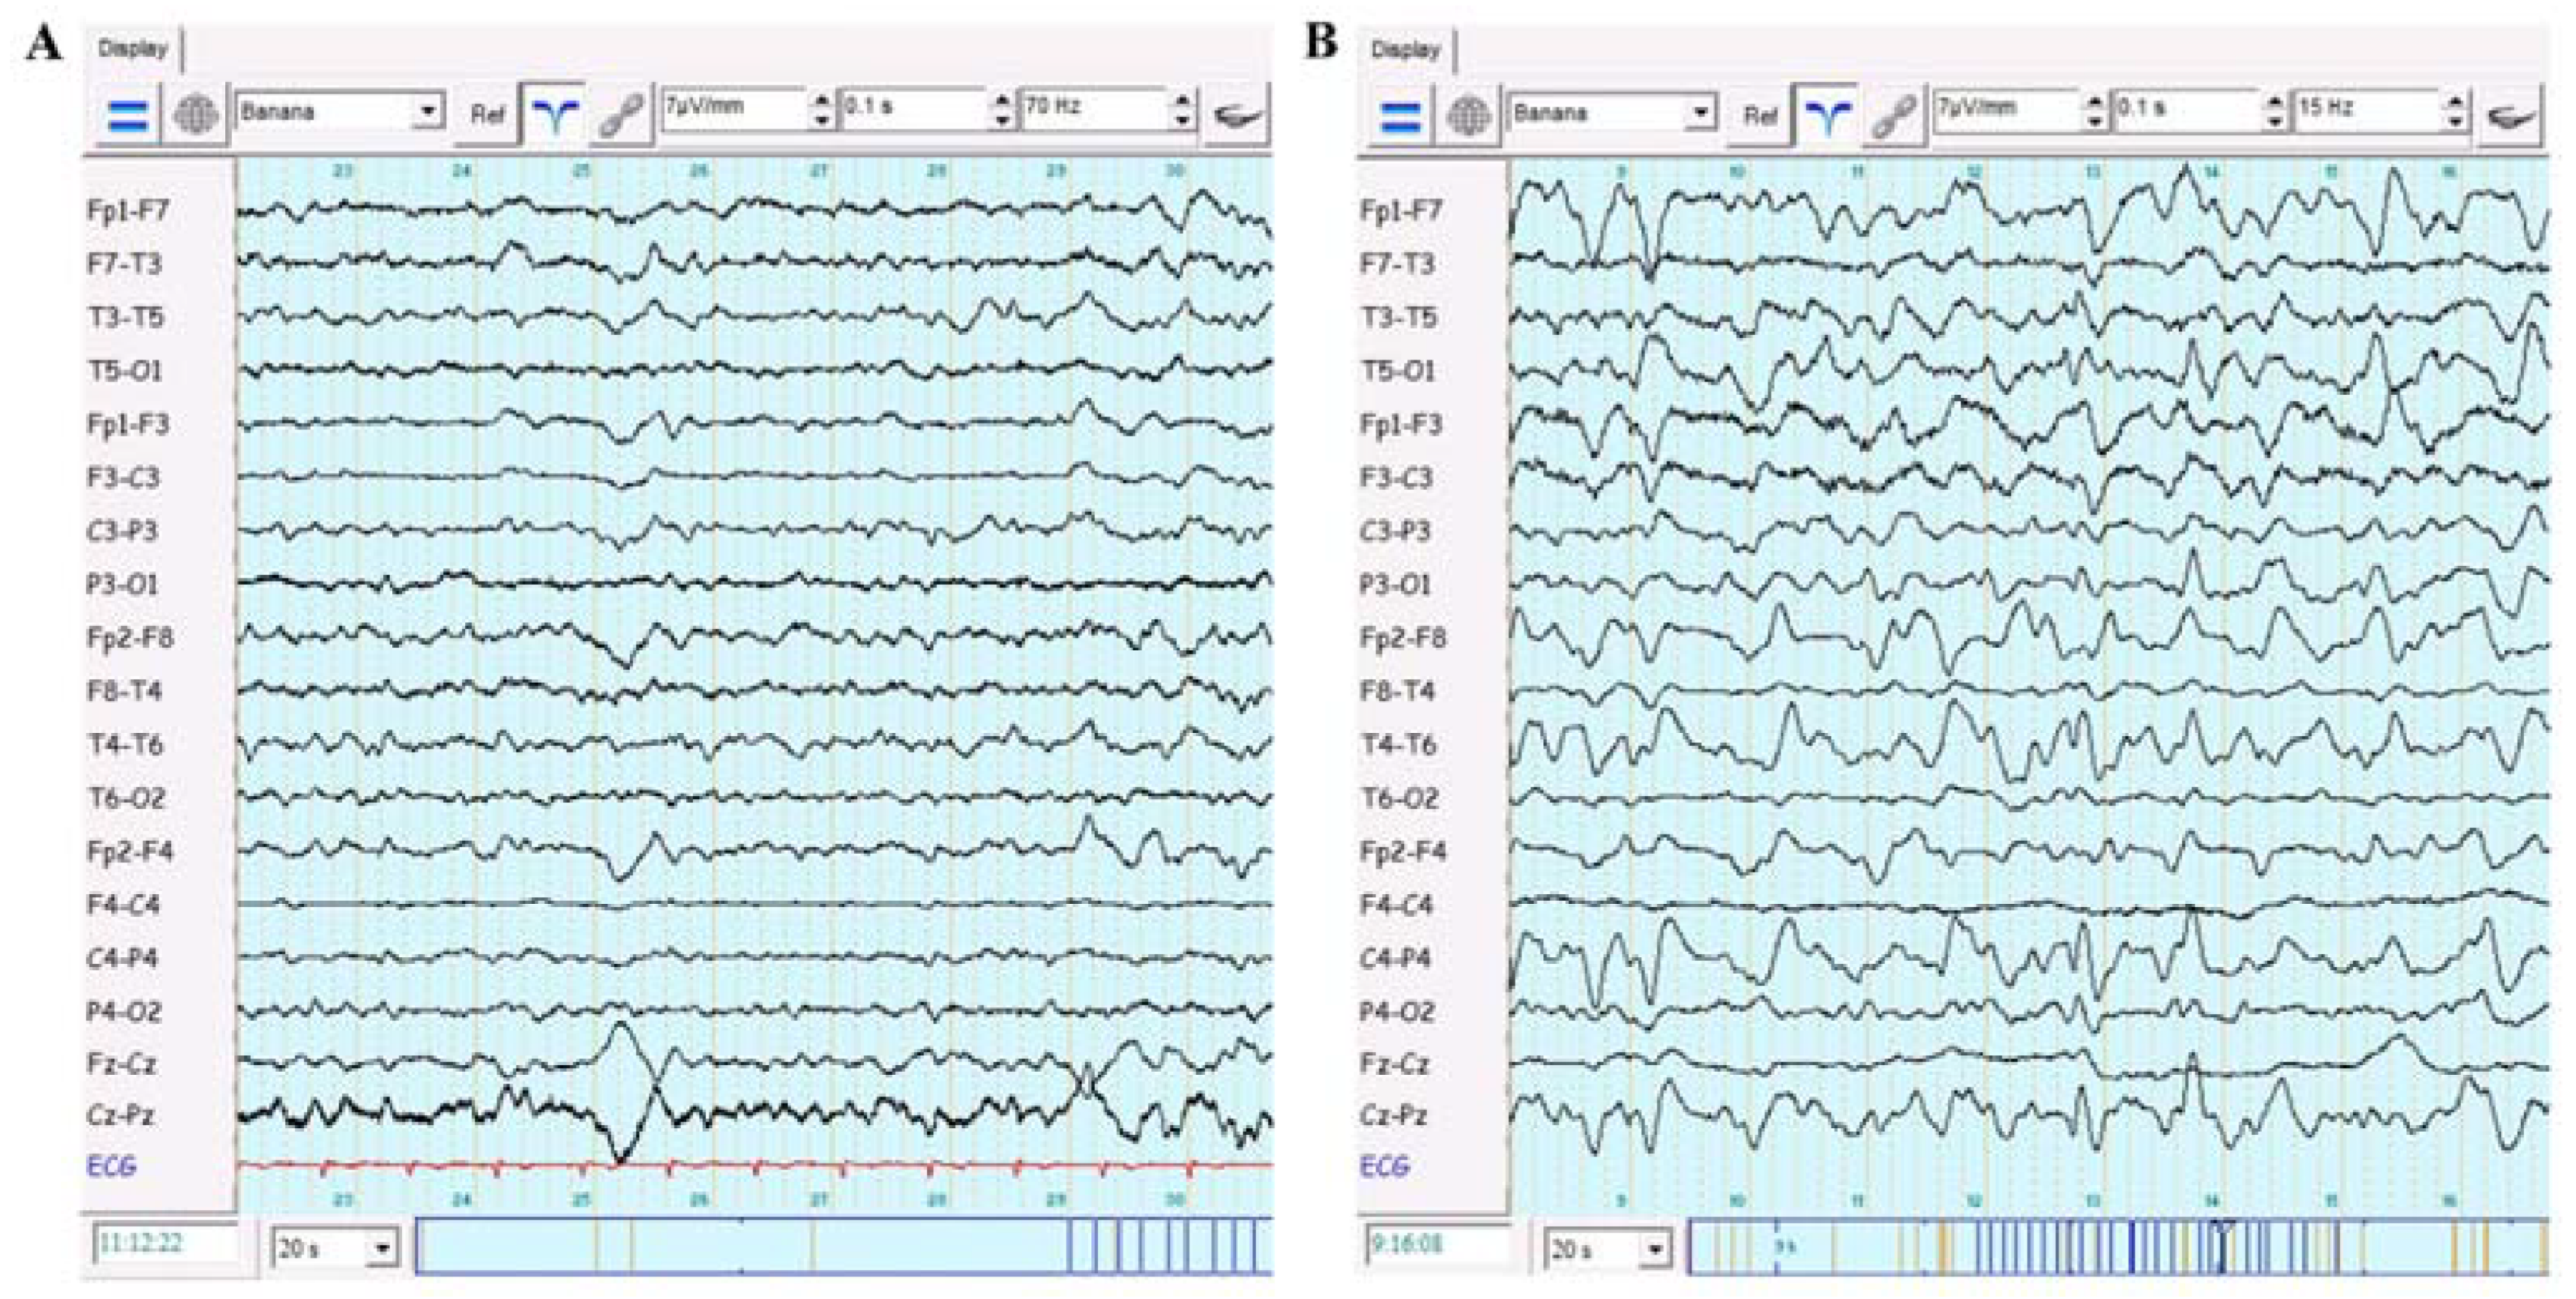

2. Case Report